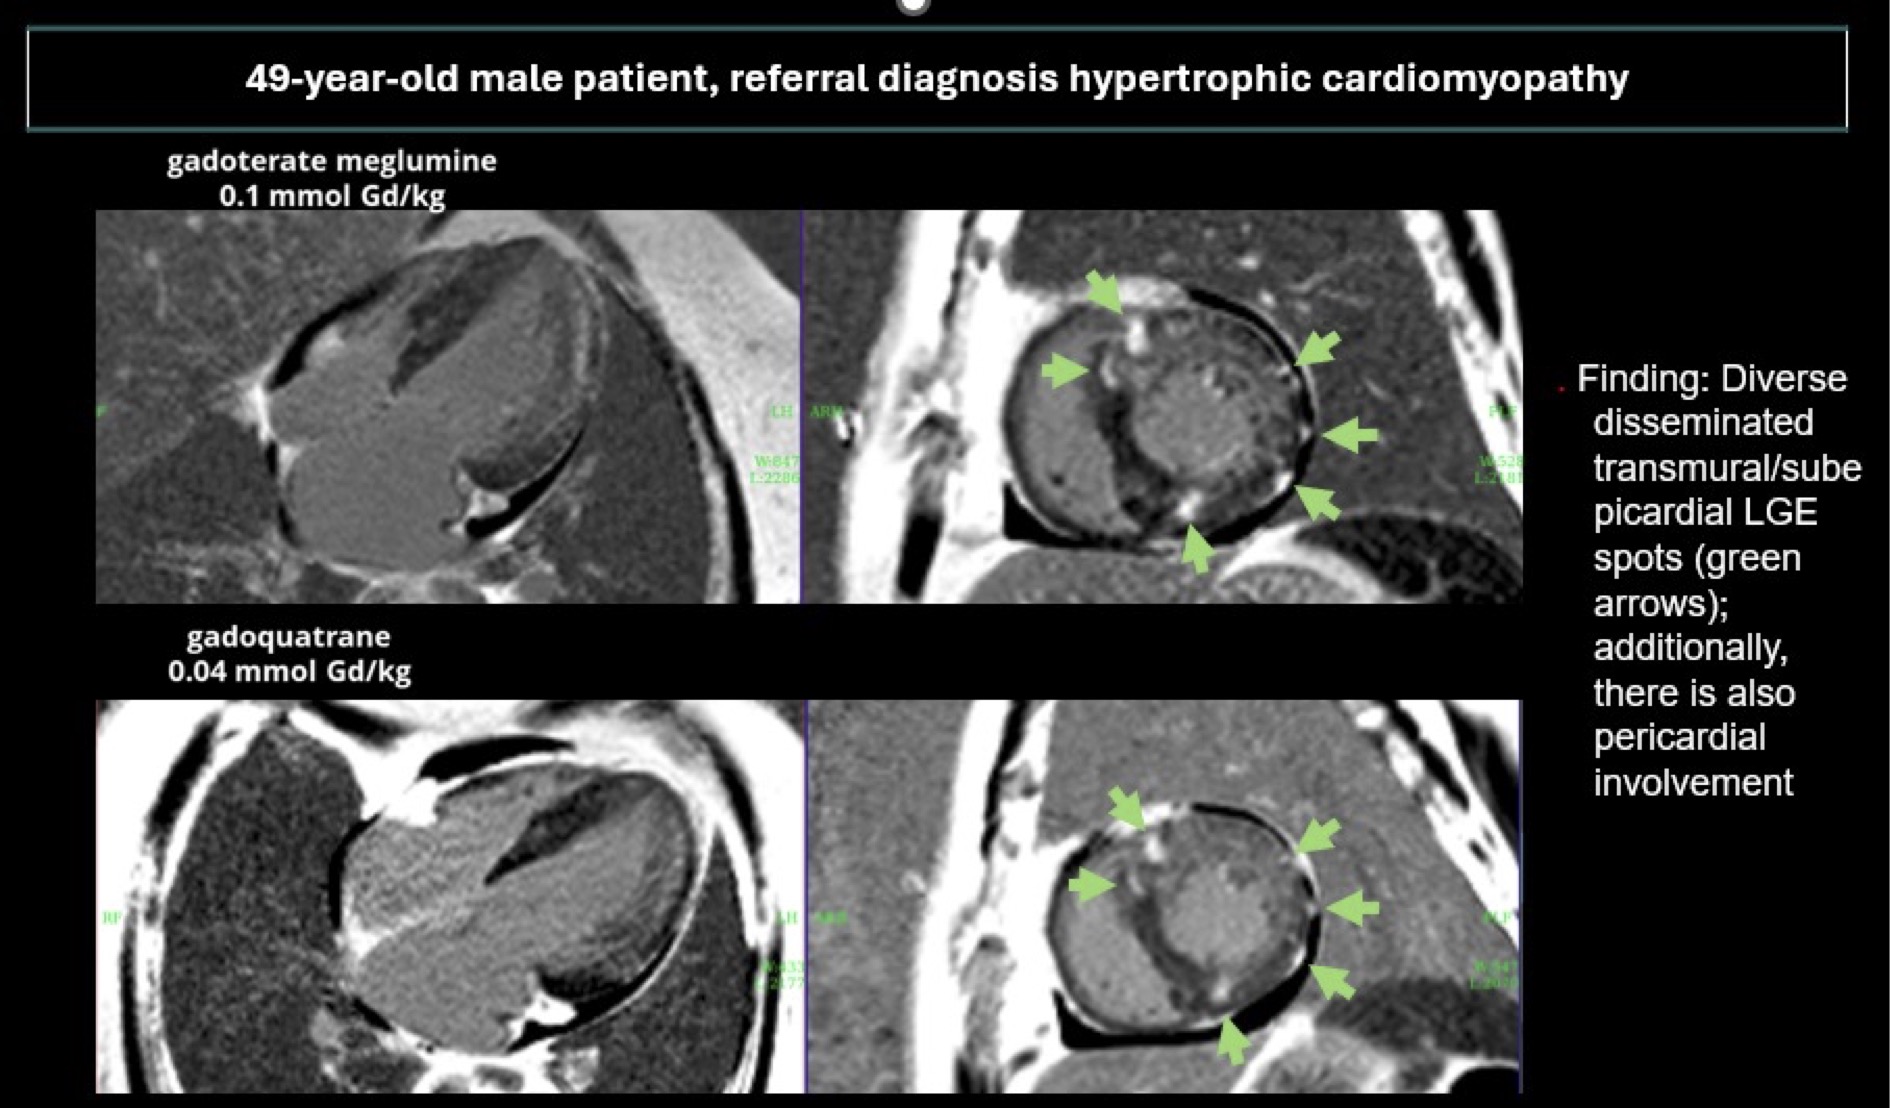

Figure 2

Figure 3.jpg)